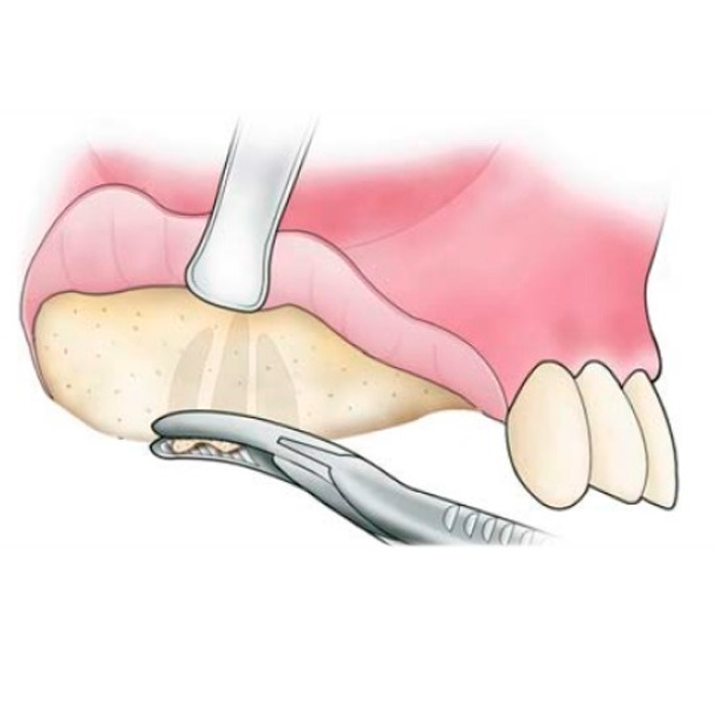

- Ver expedienteCirugía Preprotésica